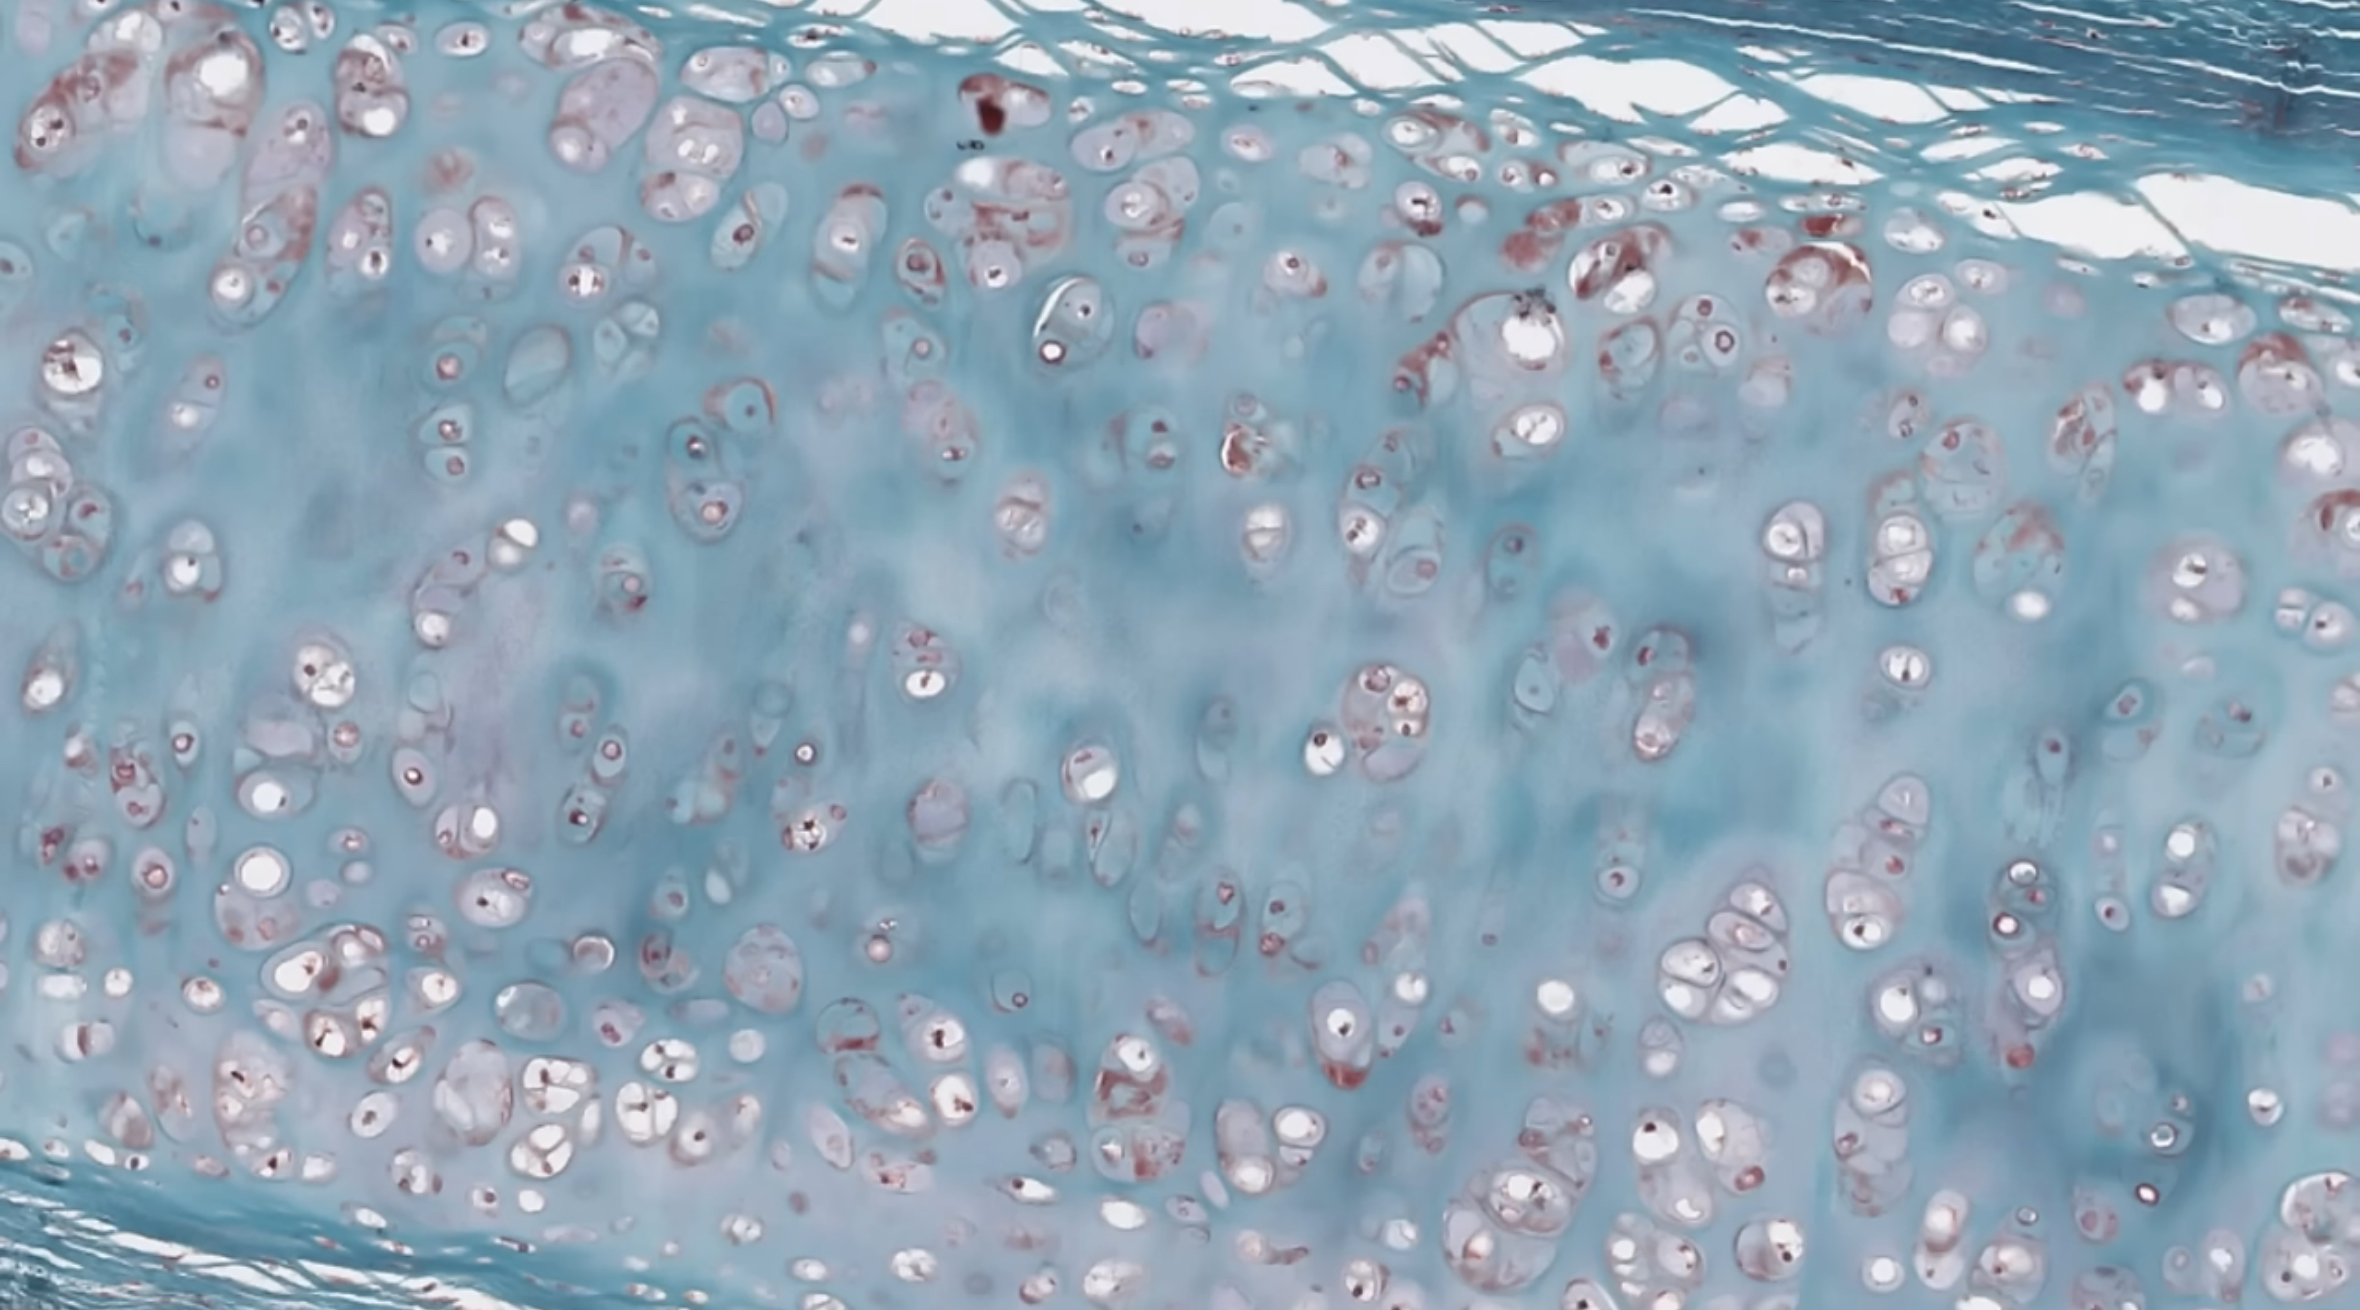

term image

1. hyaline cartilage

2. elastic cartilage

3. fibrocartilage

<ol><li><p>hyaline cartilage</p></li><li><p>elastic cartilage </p></li><li><p>fibrocartilage</p></li></ol><p></p>